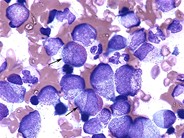

Left shifted myelopoiesis with toxic granulation - 1.

Left shifted myleopoiesis with toxic granulation is noted as part of a reactive process in this bone marrow aspirate from a child with neuroblastoma. No tumor was detected in the marrow.